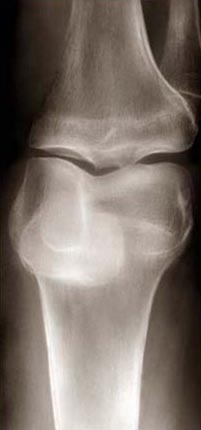

Body / Self (Knee)